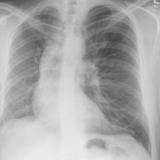

Hypoplastic Rt lung

Date: 03/29/2014

Views: 3180